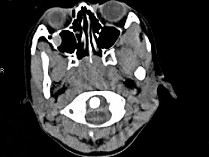

4.女,8歲,頭痛,鼻塞半年余,CT如圖所示,最可能診斷為  (    )

正確答案:C